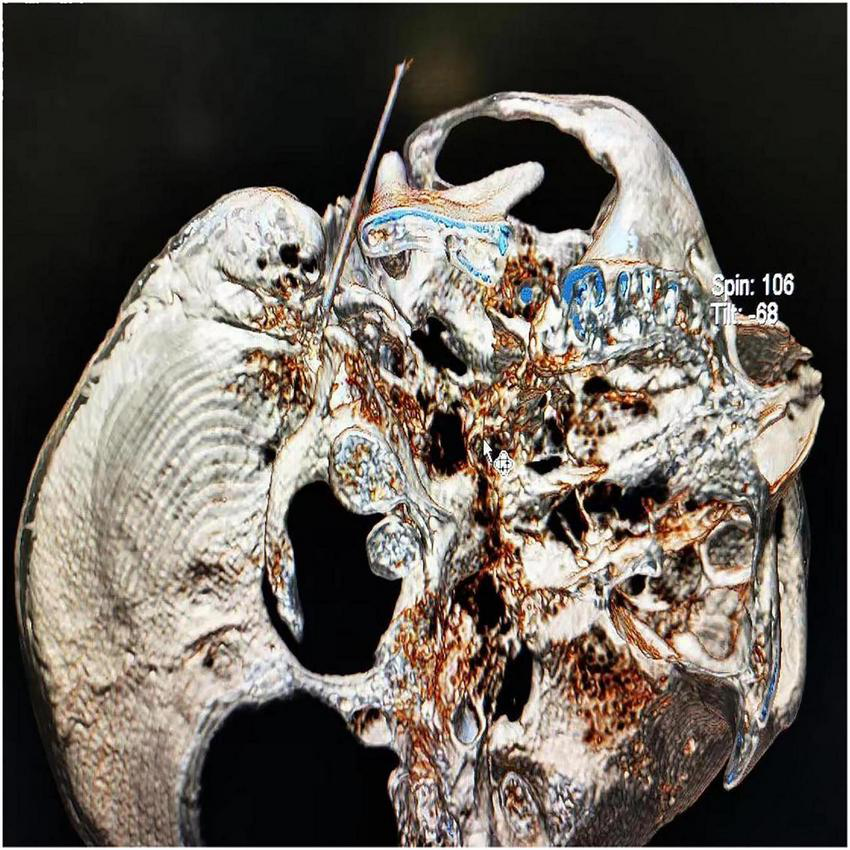

The CT layer with the stylomastoid foramen and without the bone barrier of the tympanic part of the temporal bone was selected as the puncture layer, and the CT measurement tool software was used to pull a straight line forward from the stylomastoid foramen. The intersection of the line and the skin is the puncture point (Figure 2). We determined the puncture depth (the distance from the puncture point to the target) and puncture angle (the angle between the puncture route and sagittal plane). After administering local anesthesia to the puncture site, a stylet 7-gauge radiofrequency needle with a length of 10 cm and an exposed end of 5 mm (Model 240100; Innomed Medical Technology Co., Ltd.) was gradually advanced toward the target under the guidance of intermittent CT inspection (Figure 3) and confirmed by three-dimensional reconstruction of CT scanning (Figure 4). The facial nerve was then stimulated with a radiofrequency probe at a frequency of 2 Hz and a current capacity of 0.5 mA (RF instrument model PMG230; Baylis Medical Co., Inc.). The positive facial muscle twitches from the stimulation indicated that the facial nerve was in close proximity (Supplementary Video 1).

FIGURE 4

Three-dimensional reconstruction of the CT scans confirmed successful puncture of the stylomastoid foramen.